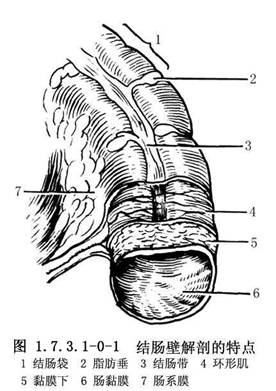

结肠长约1.5m,约为小肠的1/4。结肠外观上有4个特征,易与小肠鉴别:①结肠带:是结肠壁纵肌层集聚而成的3条纵带,自盲肠端至乙状结肠直肠交界处;②结肠袋:因结肠带较短而结肠较长,引起肠壁皱缩成囊状;③脂肪垂(肠脂垂):是结肠的脏层腹膜下脂肪组织集聚而成,沿结肠带分布最多,在近端结肠较扁平,在乙状结肠则多呈带蒂状;④肠腔较大,肠壁较薄(图1.7.3.1-0-1)。结肠分为盲肠、升结肠、横结肠及乙状结肠等。结肠的功能主要是吸收水分和储存粪便(图1.7.3.1-0-2)。吸收作用以右半结肠为主,因其内容物为液体、半液体及软块样,故主要吸收水分、无机盐、气体、少量的糖和其他水溶性物质,但不能吸收蛋白质与脂肪。若右半结肠蠕动降低,则加强吸收能力;横结肠内若有硬的粪块,常导致便秘。左半结肠的内容物为软块、半软块或固体样,故仅能吸收少量的水分、盐和糖。若左半结肠肠蠕动增强,则降低吸收能力,常有腹泻或稀便。结肠黏膜仅能分泌黏液,使黏膜润滑,以利粪便通过。切除结肠后,吸收水分的功能逐渐由回肠所代替,故主要对切除结肠的任何部分,甚至全部,也不致造成永久性代谢障碍。